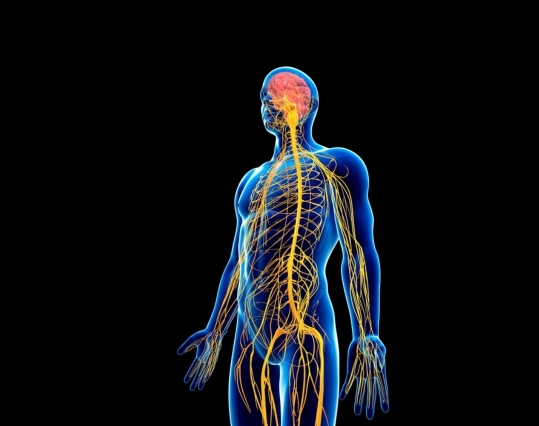

To fully grasp the benefits of CBD use, it’s vital to understand the endocannabinoid system. Also referred to as the ECS, it is essentially a complex regulatory system within the human body that is known to play a crucial role in maintaining homeostasis.

Endocannabinoids are naturally occurring compounds that are produced by the body. They bind to cannabinoid receptors, which are found throughout the central nervous system and peripheral nervous system. These receptors are like locks, and endocannabinoids are the keys that fit into them. When endocannabinoids bind to the receptors, signals are sent to regulate functions such as mood, pain, and appetite.

There are two main types of cannabinoid receptors in the ECS, known as CB1 and CB2 receptors. CB1 receptors are predominantly situated in the central nervous system, while CB2 receptors are primarily located in the peripheral tissues and immune cells. These receptors are responsible for mediating the effects of endocannabinoids and external cannabinoids, such as CBD.

The endocannabinoid system also includes other components, such as transporters and lipid signalling molecules. These components work together to maintain balance and homeostasis in the body.